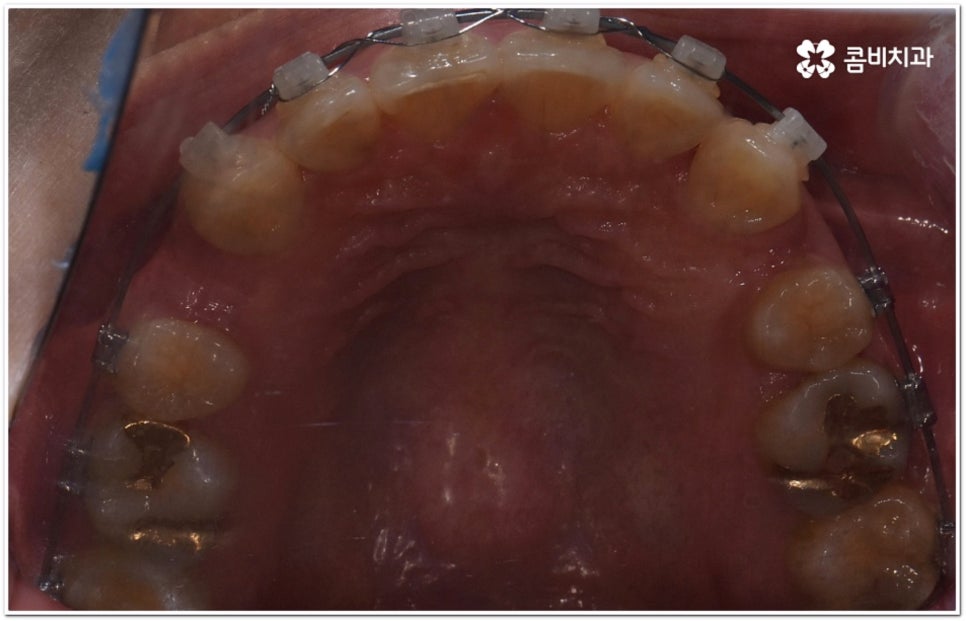

또한 구조적인 부분에 원인이 있었다면 교정 치료를 받은 후에도 원래대로 치열이 돌아가려고 하는 회귀 경향이 좀 더 강하게 일어날 수 있어요. 그렇기 때문에 치과에서 말씀드린 유지 장치를 잘 착용하면서 사후 관리를 철저하게 해 줘야 보다 오랜 시간 동안 바른 치열을 유지하면서 이를 건강하게 사용할 수 있습니다.

가철식(뺐다 꼈다 할 수 있는) 유지 장치는 눈에 잘 띄지 않고 식사를 할 때나 중요한 자리에서 잠깐씩 뺄 수 있다는 장점을 가지고 있지만 착용하는 시간이 부족하게 되면 혹여 치열이 다시 삐뚤어지거나 교합이 어긋나게 되어 심한 경우 재교정을 받아야 하는 상황까지도 이를 수 있기 때문에 교정이 끝난 초기에는 환자분들께서 주의를 기울여서 불가피한 경우가 아니라면 계속해서 착용을 해주시길 권고드리고 있어요. 그 이후에는 치료하신 치과의 안내에 따라 착용 시간을 줄여가면서 정기적인 검진을 받으시면서 관리를 해주시는 게 좋아요. 이에 반해 고정식 유지 장치는 착용 시간을 신경쓰지 않아도 되지만 부착시킨 철사로 인해 칫솔질이 어려워지고 치석이 잘 생기는 등 위생 문제가 발생할 수 있다는 점을 유의해야 하므로 주기적으로 검진을 받으면서 스케일링 치료를 통해 구강 내 위생 관리를 철저하게 해 주면 도움이 될 거예요. 가장 좋은 것은 고정식 유지장치와 가철식 유지장치를 둘 다 착용을 하시는 게 도움이 되므로, 치료를 담당하시는 원장님과 자세히 상담받아보시길 권장 드려요.